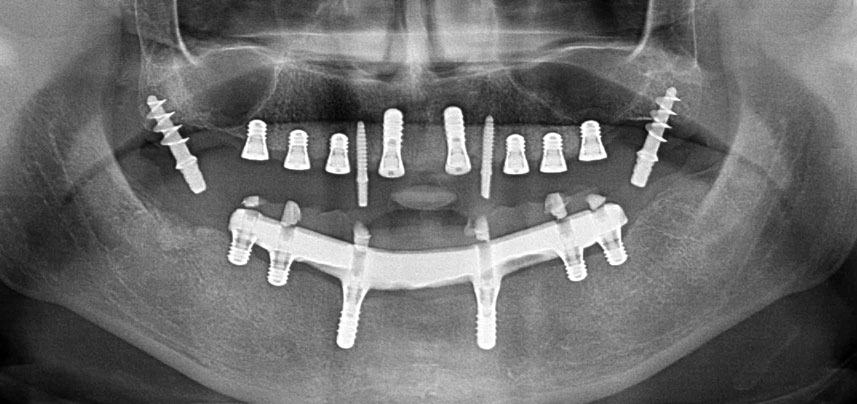

A 41-year-old patient without systemic particularities lost all her teeth due to periodontitis and caries. Finally she had to wear mucosa-supported total dentures in both jaws, with great masticatory difficulties due to the ill-fitting prostheses. The patient decided to have implants placed to support a bar-retained fixed CAD/CAM prosthesis in the mandible.

Three years later it was time for a maxillary denture of the same type. Based on CBCT planning sinus augmentation was avoided with the aid of short implants, and a surgical template was used to transfer the planned positions to the alveolar ridge (Figs. 1 and 2).

Due to the relatively hard bone (D2) in this area, the 10 mm long implant sites at positions 11 and 21 were finalized with a 4 mm diameter rotary drill, in combination with a W&H WS-75 L surgical contra-angle handpiece, the W&H Implantmed implant motor and the optional W&H Osstell ISQ module. In contrast, due to the soft bone the posterior sites were prepared to a final 3 mm diameter using the Piezomed I3P instrument. The implants were finally placed transgingivally to osseointegrate for three months (Figs. 6-10). The existing denture was retained on four provisional implants (Fig. 8).